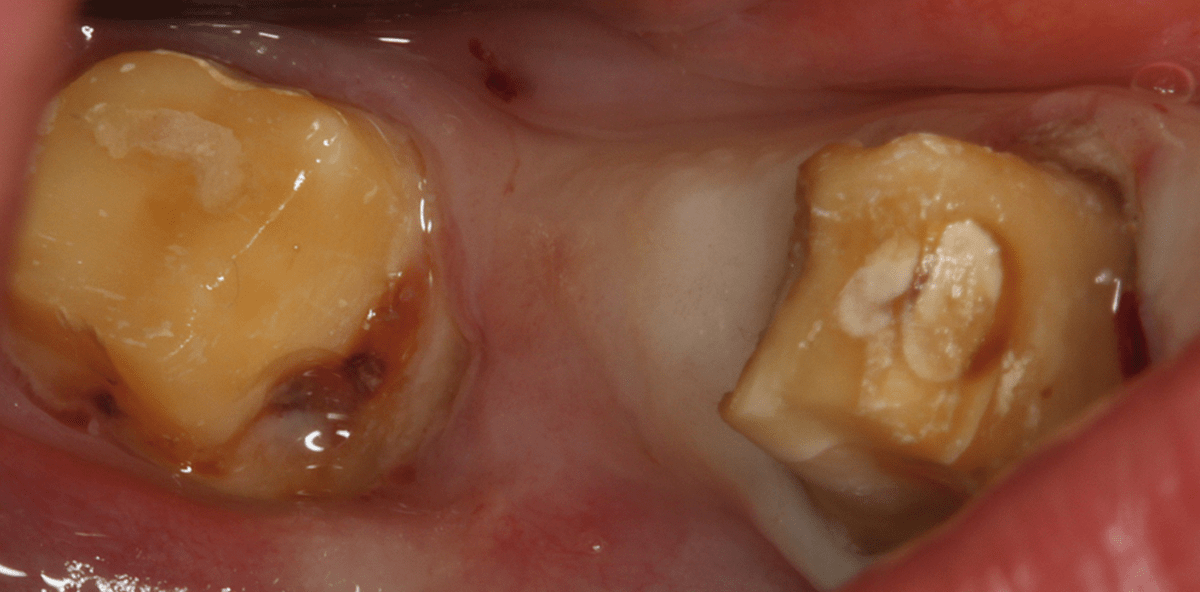

Die Abbildungen 3 bis 6 beschreiben den Behandlungsverlauf Regio 48–46 einer zum Zeitpunkt der Reevaluation 52-jährigen Patientin mit chronischer Parodontitis (CP). Die vorherige supragingivale antiinfektiöse Therapie umfasste mehrere Sitzungen. Neben der Dokumentation des Papillenblutungs- bzw. Plaqueindex, Mundhygieneinstruktionen, professioneller Zahnreinigung, Kronen- und Füllungsrekonturierung erfolgte die Depuration aller Stellen mit Sondierungstiefen größer 3 mm mit Sondierungsblutung mit speziellen Handinstrumenten. Abbildung 3 zeigt die klinischen Parameter Regio 48–46 mit Sondierungstiefen (ST) bis 7 mm mit Sondierungsblutung (SB). Das präoperative Röntgenbild zeigt einen ein- und dreiwandigen parodontalen Knochendefekt am Zahn 48. In der Praxis wurde unter Anästhesie ein mikrochirurgischer Lappen ohne Entlastungsinzisionen an den Zahn 48 gebildet und die Wurzeloberflächen erneut unter Sicht mit speziellen Instrumenten geglättet. Anschließend wurde eine Knochenersatzimplantation mit GUIDOR® easy-graft® CRYSTAL durchgeführt. Besonders an der mesialen Wurzel des Zahnes 48 zeigte sich ein tiefer intraalveolärer zwei- und dreiwandiger Kombinationsdefekt (Abb. 4). Es wurde keine postoperative Antibiotikatherapie empfohlen. Die Wundheilung verlief unkompliziert und es zeigte sich ein Early-Healing-Index von I nach einer und zwei Wochen (Wachtel et al., 2003). Abbildung 5 zeigt die klinische Situation bei der postoperativen Kontrolle nach drei Monaten. Alle Sondierungswerte lagen  zu diesem Zeitpunkt bei bis zu 4 mm ohne Sondierungsblutung. Zahn 48 hatte nach diesem Befund eine gute Prognose. Die Röntgendokumentation zeigt eine komplette Auffüllung des Defektes nach drei Monaten ohne Komplikationen und ohne Bildung von Gingivarezessionen. Die korrektive Therapie der angulären Knochendefekte konnte durch Röntgenverlaufsdokumentation und die klinischen Befunde belegt werden. Auch nach zwölf Monaten zeigte sich eine komplette Defektauffüllung und Knochenintegration des Materials ohne Komplikationen (Abb. 6).

Abbildung 7 zeigt die klinischen Parameter Regio 14–16 bei einem zum Zeitpunkt der Reevaluation 63-jährigen Patienten mit chronischer Parodontitis (CP). Bei Zahn 15 liegt eine Sondierungstiefe von bis zu 7 mm mit Sondierungsblutung vor. Das präoperative Röntgenbild zeigt einen kombinierten zwei- und dreiwandigen parodontalen Knochendefekt im Interdentalbereich der Zähne 16 und 15 (Abb. 7). In der Praxis wurde unter Anästhesie ein mikrochirurgischer Papillenerhaltungslappen ohne Entlastungsinzisionen an den Zähnen 15 und 16 gebildet und die Wurzeloberflächen erneut unter Sicht mit speziellen Instrumenten geglättet. Anschließend wurde eine regenerative Parodontaltherapie mit einer Kombination von Schmelzmatrixproteinen (Straumann® Emdogain®) und Knochenersatzmaterial (GUIDOR® easy-graft® CRYSTAL) durchgeführt. Abbildung 8 zeigt die intraoperative Situation und die richtige Reihenfolge bei der regenerativen Therapie, in der zuerst die Schmelzmatrixproteine und anschließend das Knochenersatzmaterial appliziert werden müssen. Aus dem Gaumen Regio 13–15 wurde ein Bindegewebetransplantat entnommen und subepithelial in der operierten Region zur Unterstützung der postoperativen gingivalen Morphologie und als natürliche Barriere eingebracht (Abb. 9). Eine Antibiotikatherapie in Form von Amoxicillin 500 mg wurde 3 x täglich über sieben Tage verabreicht. Die Regeneration der Knochendefekte konnte durch Röntgenverlaufsdokumentation und die klinischen Befunde belegt werden. Nach einer und zwei Wochen zeigten sich keine Wundheilungsstörungen und keine Bildung von Gingivarezessionen (Abb. 10). Die postoperative röntgenologische Kontrolle nach sechs Monaten zeigte eine komplette Regeneration des Defektes und Integration des Knochenersatzmaterials ohne Komplikationen (Abb. 11). Auch die klinischen Parameter zeigten zum Zeitpunkt nach sechs Monaten eine deutliche Verbesserung mit Sondierungstiefen bis maximal 4 mm ohne Sondierungsblutung und Gingivarezessionen von maximal 2 mm.

Abbildung 12 zeigt die klinischen Parameter Regio 35–37 bei einer zum Zeitpunkt der Reevaluation 47-jährigen Patientin mit chronischer Parodontitis (CP). Bei Zahn 35 liegt eine Sondierungstiefe von bis zu 10 mm mit Sondierungsblutung vor. Der Zahn war devital ohne Perkussionsempfindlichkeit und ohne Beweglichkeit. Das präoperative Röntgenbild zeigt einen kombinierten zwei- und dreiwandigen parodontalen Knochendefekt mit einer tiefen intraossären Komponente und Destruktion des bukkalen Alveolarknochens bis zum apikalen Drittel der Wurzeloberfläche. Nach der endodontischen Therapie wurde die Parodontalchirurgie durchgeführt. Unter Anästhesie wurde ein vollmobilisierter Mukoperiostlappen mit vereinfachten Papillenerhaltungslappen ohne Entlastungsinzisionen an den Zahn 35 gebildet und die Wurzeloberflächen erneut unter Sicht mit speziellen Instrumenten geglättet (Abb. 13). Anschließend wurde eine regenerative Parodontaltherapie mit einer Kombination von Schmelzmatrixproteinen (Straumann® Emdogain®) und Knochenersatzmaterial (GUIDOR® easy-graft® CRYSTAL) durchgeführt. Zuerst wurden die Schmelzmatrixproteine und anschließend das Knochenersatzmaterial appliziert. Der fehlende Knochen auf der bukkalen Seite wurde mit dem Material ersetzt. Eine Antibiotikatherapie in Form von Amoxicillin 500 mg 3 x täglich über sieben Tage wurde verabreicht. Der Lappen wurde repositioniert und mit atraumatischem Nahtmaterial vernäht.  Nach einer und zwei Wochen zeigten sich keine Wundheilungsstörungen und keine Bildung von Gingivarezessionen (Abb. 14).